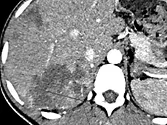

Figure 7. Carcinome hépatocellulaire traité par sorafénib.

Sur l’examen initial (A), la lésion présente deux compartiments sur cette image d’IRM au temps artériel l’un nécrotique, l’autre qui se rehausse, appelé tumeur « viable ».

B. Mesure selon mRECIST du plus grand diamètre de la lésion viable.

C et D. Après quatre mois de chimiothérapie, le compartiment viable de la tumeur passe de 37 à 24 mm, soit une diminution de 35 %. Il s’agit donc d’une réponse partielle, alors que le volume total de la lésion n’a pas changé.

Selon RECIST 1,1, la réponse aurait été « SD »